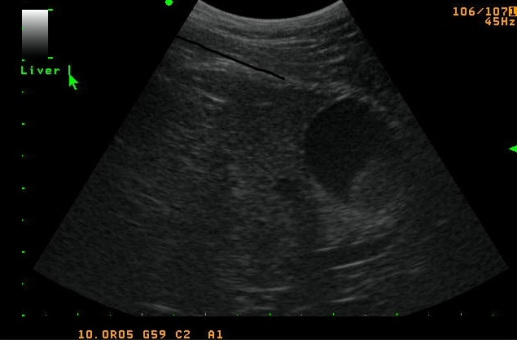

Ultrasounds

Ultrasound examination provides a noninvasive diagnostic tool using painless sound waves to evaluate internal organs and tissue structure. We can visualize most of the internal organs and capture the image. Those images along with all related test results, are digitally sent to board certified internal specialist or cardiologists who read the images. After their review they send us their interpretation which we will then pass on to you, the owner. The rest of the ultrasound study may warrant further diagnosis such as an ultrasound guided biopsy. This provides a less invasive means of obtaining deeper tissue samples for cytological evaluation.